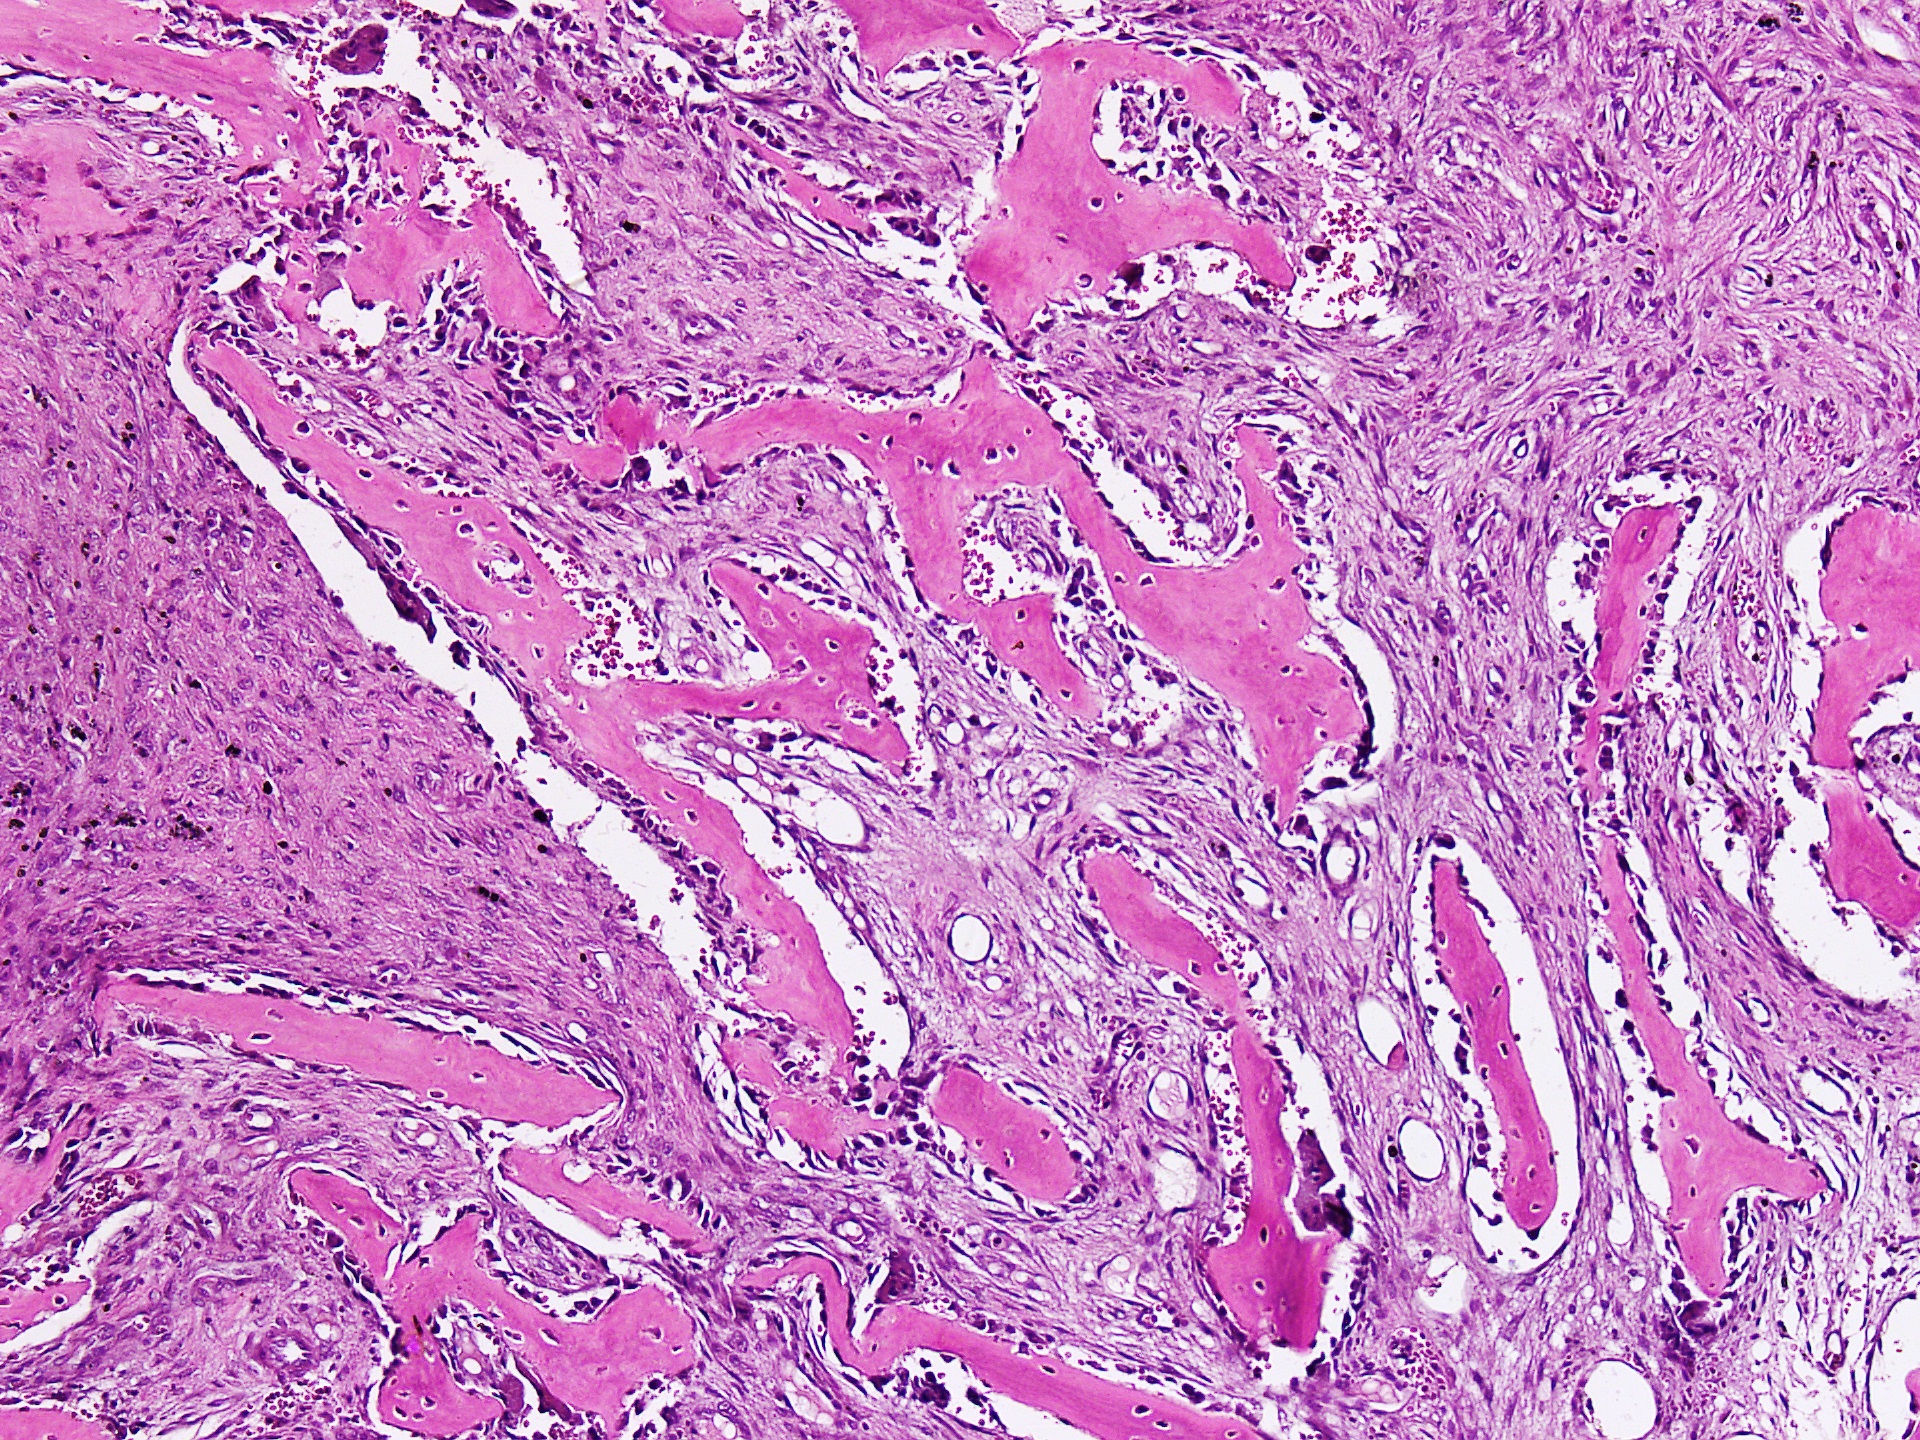

Osteitis fibrosa cystica

- Increased number of osteoclasts erode bone matrix and mobilize calcium salts, particularly in the metaphysis of long tubular bones

- Bone resorption is accompanied by increased osteoblastic activity and the formation of new bony trabeculae

- Gross description: the cortex is thinned and the marrow contains increased amounts of fibrous tissue accompanied by foci of hemorrhage and cyst formation

- Microscopic (histologic) description: increased bone cell activity, peritrabecular fibrosis, cystic brown tumors (Kumar: Robbins & Cotran Pathologic Basis of Disease, 10th Edition, 2020)

Microscopic (histologic) description

- Lobular pattern composed of groups and clusters of osteoclast-like multinucleated giant cells

- Vascular fibroblastic stroma

- Hemorrhage and hemosiderin deposits

- Tunneling resorption of adjacent uninvolved bone (J Int Oral Health 2015;7:50)

Microscopic (histologic) images